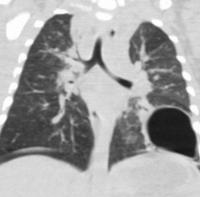

Patients with ADHIES suffer from immune dysregulation leading to susceptibility to pulmonary infections, and subsequent development of anatomic complications in the form of pneumatoceles, which are large air filled sacs that form in the lung as a result of prior infection. These pneumatoceles then become sites where opportunistic organisms, such as fungal infections, can occur, and lead to life long morbidity for these patients. Based on data obtained in our lab, we hypothesize that fibroblast dysfunction may be the etiology of pneumatoceles. This study is being conducted in collaboration with the Prince Lab, a world leader in pulmonary infection, and is funded by the Job Research Foundation.